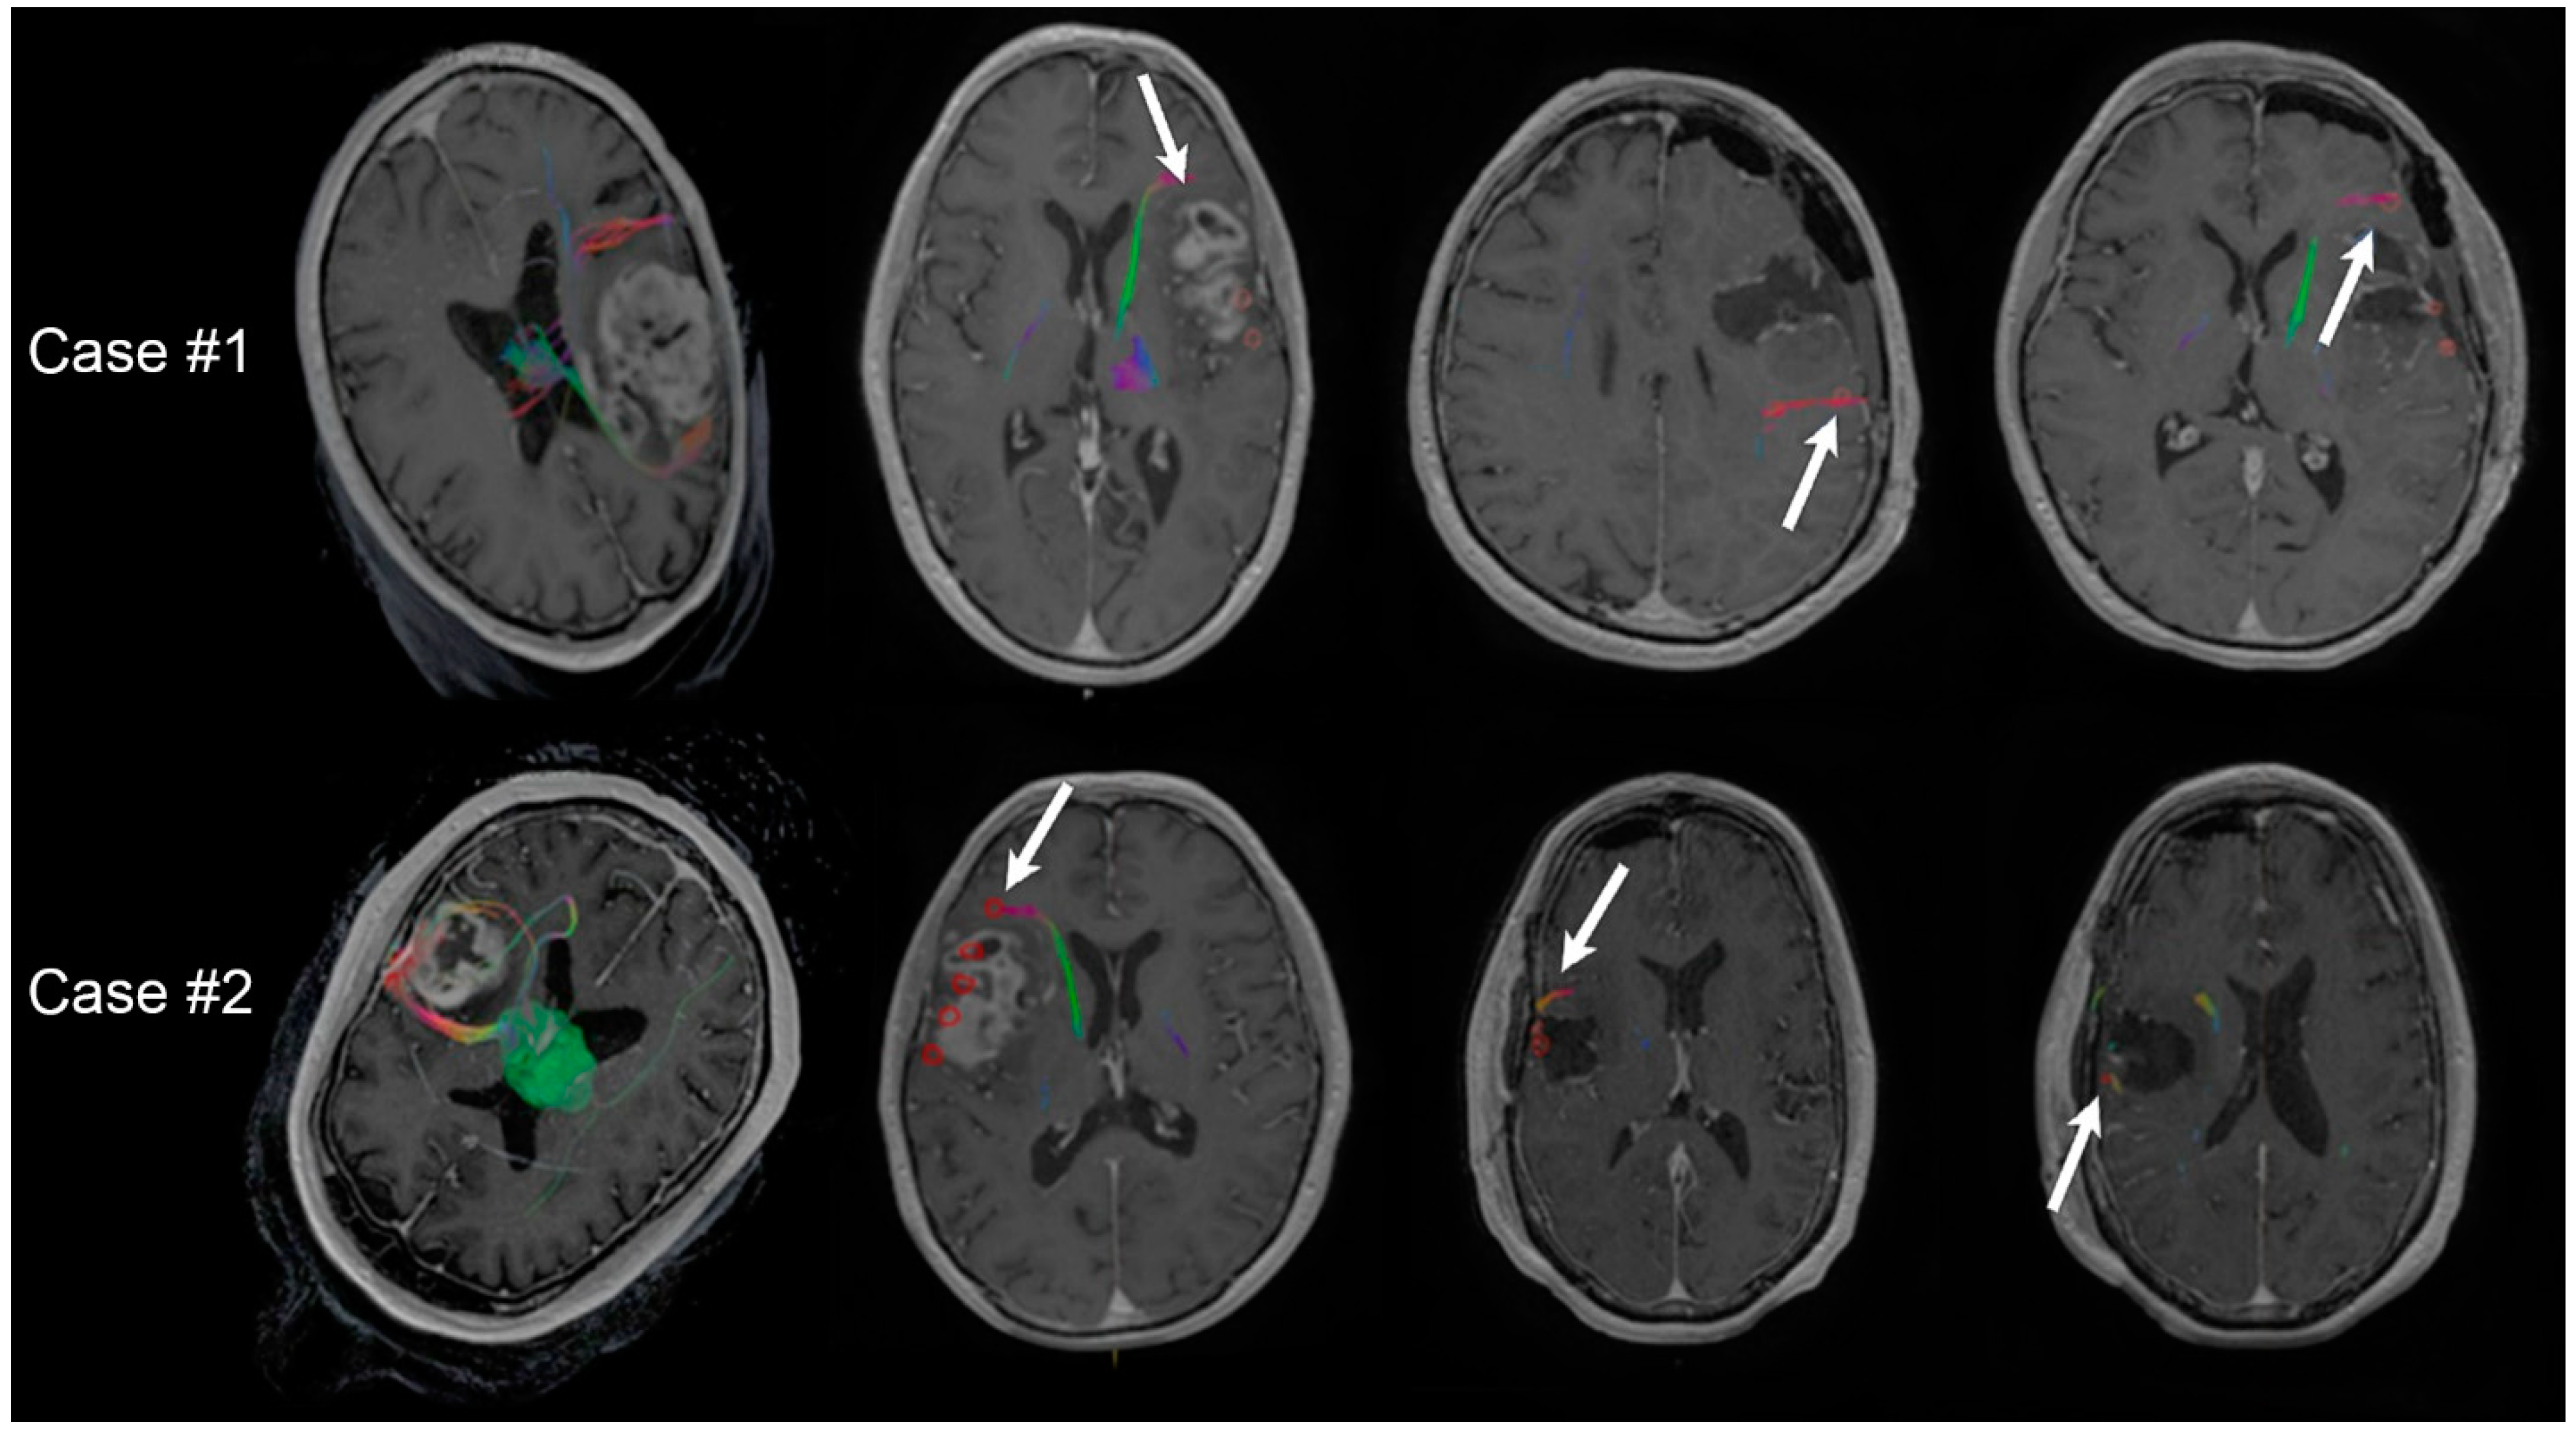

2.1. Transcranial Magnetic Stimulation

2.2. Diffusion Tensor Imaging

2.3. Perioperative Overlays